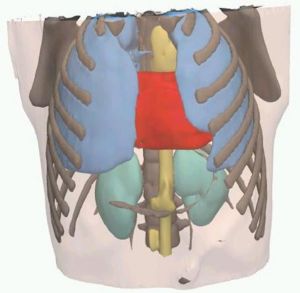

MRI with labeled structures from atlas registered to the CBCT. Registration was carried out with the open source imaging tool 3D Slicer, Version 4.4.0. |